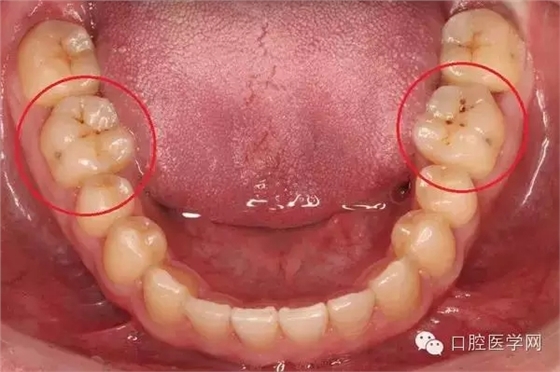

另一種則是牙齒出現(xiàn)了或深或淺的齲壞,從外面看就表現(xiàn)為一個黑點,通常位于窩溝點隙(牙面上點狀或線狀凹陷)。齲齒的罪魁禍?zhǔn)资强谇恢械哪承┘?xì)菌,但它們破壞牙齒也是需要時間的,從初期的變色到最終形成齲洞,通常需要1年半到兩年。在此期間,我們多留心自己的牙齒,完全可能把齲壞扼殺在萌芽階段。如何才能及時發(fā)現(xiàn)這種隱匿的蛀牙呢?找位好牙醫(yī),半年檢查牙齒!

一旦確認(rèn)牙齒上的小黑點是齲齒就應(yīng)該盡早修補,以阻止病變的發(fā)展。如果任由其繼續(xù)發(fā)展就會變成明顯的齲洞,這時患者會對冷熱酸甜等食物刺激敏感;當(dāng)損傷進一步到達牙髓(即老百姓說的“牙神經(jīng)”),就會疼痛難忍,嚴(yán)重影響日常生活。臨床上見到很多人都會等到牙痛得受不了,才到醫(yī)院就診。這時通常不能靠單純補牙來解決問題,可能還要做根管治療甚至拔除患牙、進行假牙修復(fù),費時費力又費錢,人還遭罪,可謂“小洞不補,大洞吃苦”。